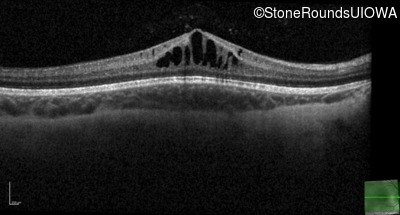

XL Retinoschisis (IIIB1)

XL Retinoschisis (IIIB1)

This 6 year old boy first experienced difficulty reading and seeing the blackboard at age 5.

| XL Retinoschisis | RS1 | Pro192His CCC>CAC | XL |